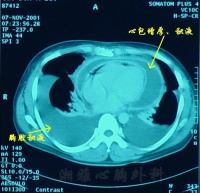

X线检查:积液量超过300毫升时,心影向两侧增大,心隔角变成锐角。超过1000毫升时,心影呈烧瓶状,并随体位而异。心脏搏动减弱或消失。

超声心动图:显示心包腔内有液化暗区,为一准确、安全、简便的诊断方法。